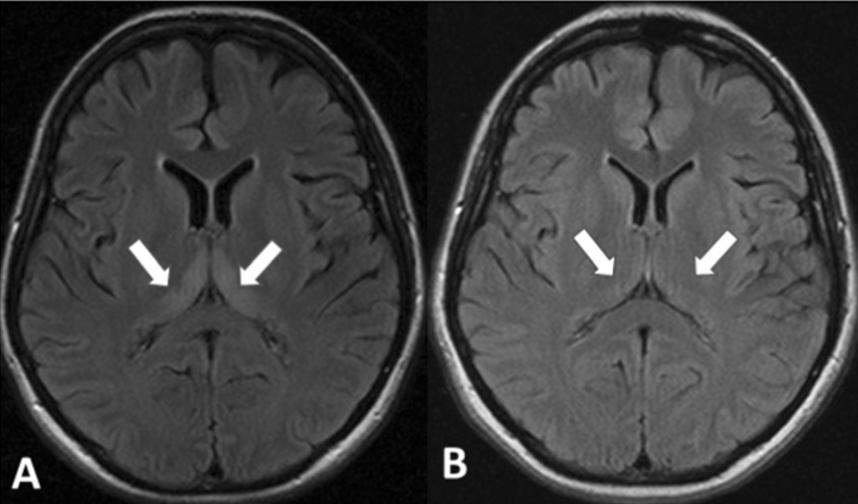

女,35歲,懷孕9周,持續(xù)性惡心、嘔吐入院,臨床表現(xiàn)為精神癥狀、嗜睡、定向力障礙。MRI提示雙側丘腦背內側Flair高信號。